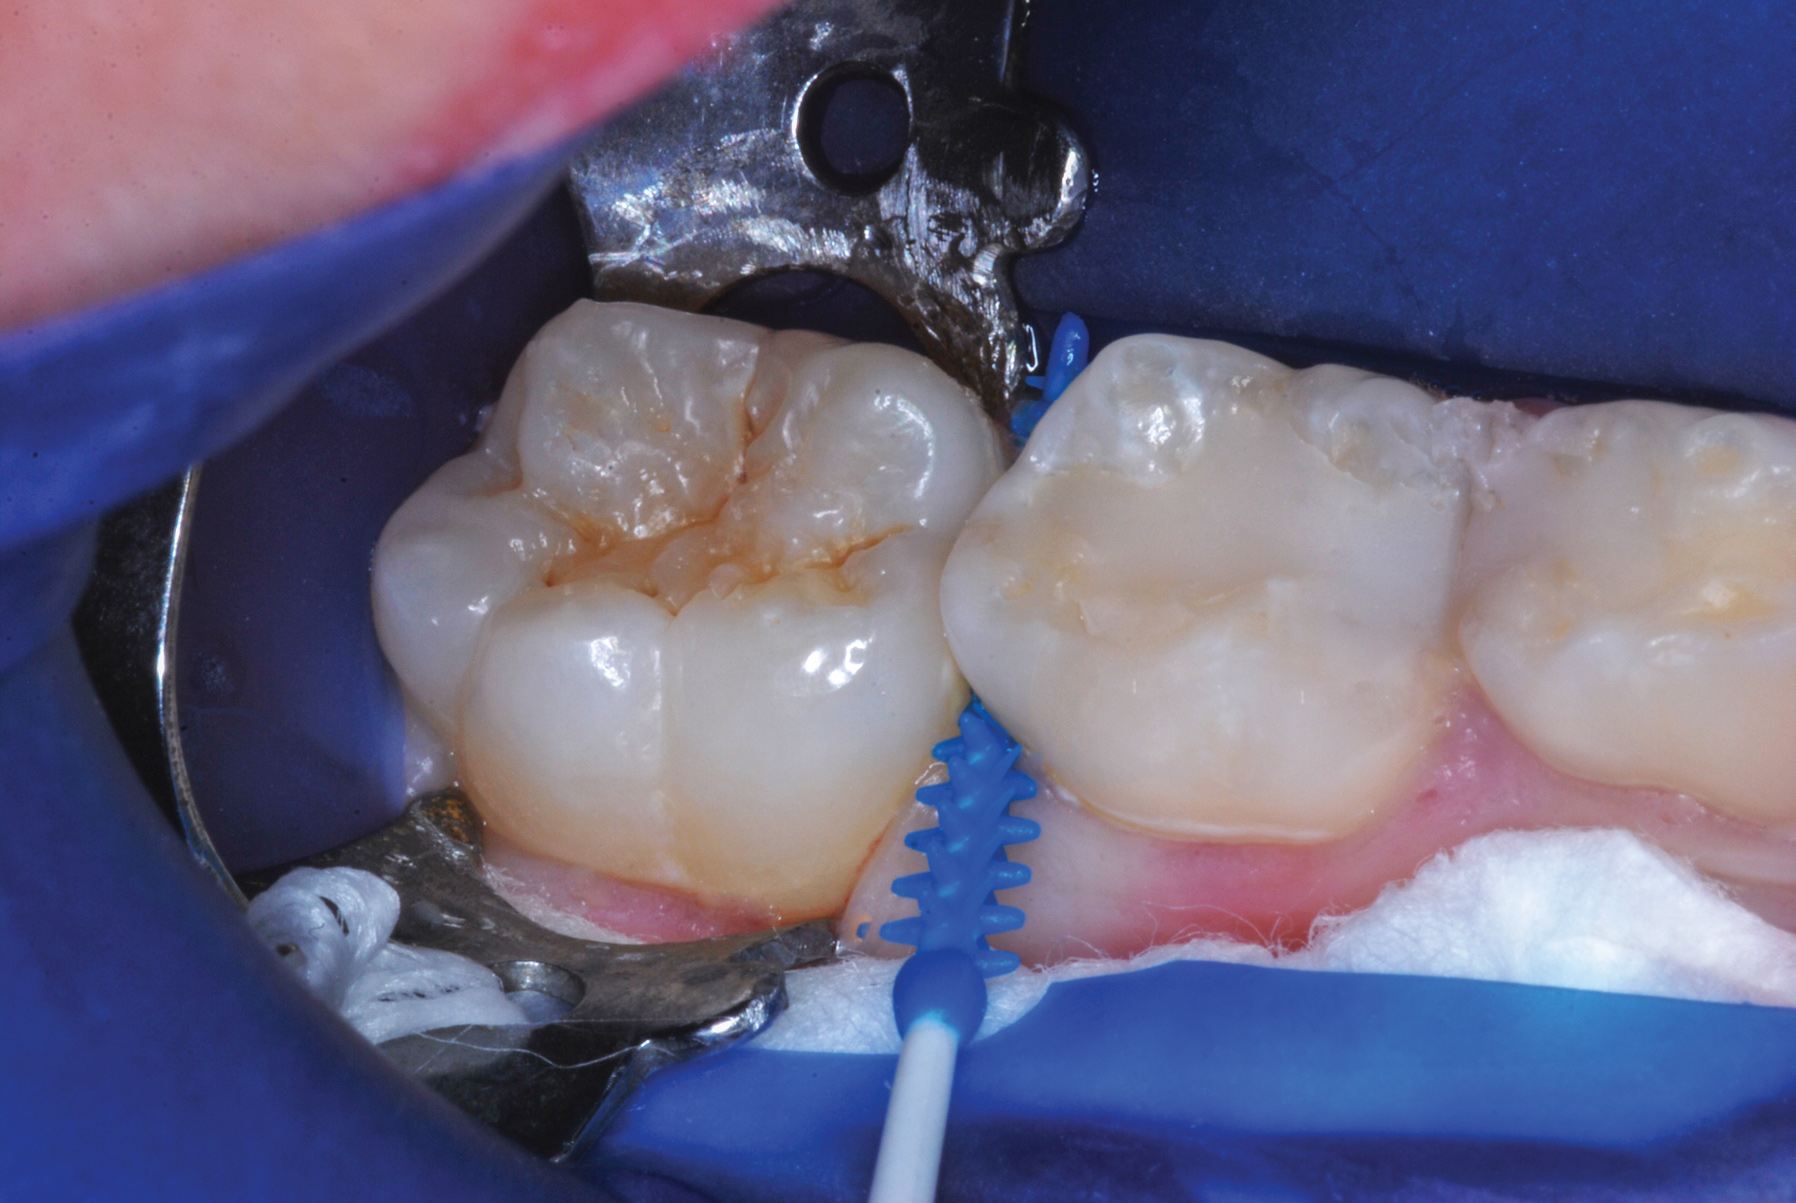

The authors' protocol for insertion of SDF-coated soft dental picks involves isolating the teeth with cotton rolls or other means, flossing the interproximal site to clear food debris and dental plaque, and then inserting a SDF-coated pick (Figure 1 and Figure 2) to saturate the contacting surfaces of the teeth with the fluid. This treatment is painless and requires no anesthetic. The pick should remain in place for at least 60 seconds and can be gently pulled in and out to agitate the fluid for enhanced surface coverage by capillary action. Additional SDF can be wiped on, using a small applicator, above the contact and in the buccal and lingual sluiceways. Excess fluid and any blood elicited may be blotted with a cotton swab. An additional 60-second insertion may be applied in the same way if there is radiographic evidence of a deeper decalcification or caries lesion. With the pick still in place, 5% (or 2.5%) fluoride varnish is painted over the treatment area, and the pick is then withdrawn.

Interproximal insertion of SDF is demonstrated in different patients in Figure 3 through Figure 11. Various diameters and brands of soft dental picks may be used depending on the closeness of the proximal surfaces and ease of insertion; for example, some picks are designed for use in wider spaces between teeth. This protocol also offers versatility. Figure 3, for example, shows the simultaneous use of three thin soft dental picks to saturate proximal surfaces with SDF in a teenaged patient; the treated regions were subsequently covered with fluoride varnish (Figure 4). This patient was initially treated in April 2019 (Figure 5), with an identical re-application 3 months later. As shown in Figure 6, the December 2019 bitewing film revealed good results with the possible exception of the contact regions of the maxillary first and second molars. New SDF application was completed in the December appointment.

Figure 7 illustrates the use of thicker picks in premolar interproximal sites. Additionally, multiple picks can be used in one quadrant or in one proximal site with good isolation to maximize fluid saturation (Figure 9), which the authors have found to be an excellent time-saving strategy. Preventive or interceptive applications of SDF may also be effectively used in interproximal sites in orthodontic patients (Figure 10).